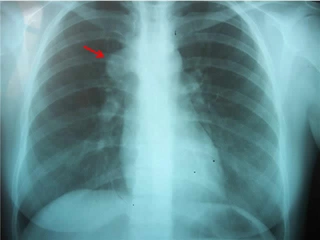

Akciğer tansiyonu, pulmoner hipertansiyon olarak da bilinen bu durum, akciğerlerdeki kan damarlarının basıncının normalden daha yüksek olması anlamına gelir. Bu rahatsızlık, kalp ve akciğer fonksiyonlarını etkileyebilir ve ciddi sağlık sorunlarına yol açabilir. Bu makalede, akciğer tansiyonunun insan sağlığı üzerindeki etkileri, belirtileri, nedenleri ve tedavi yöntemleri detaylı bir şekilde ele alınacaktır. Akciğer Tansiyonu Nedir?Akciğer tansiyonu, akciğerlerdeki kan damarlarındaki basıncın yükselmesi sonucu ortaya çıkar. Normalde, akciğerlerdeki kan damarlarının basıncı 8-20 mmHg arasında olmalıdır. Ancak bu değerlerin üzerinde bir ölçüm, pulmoner hipertansiyon olarak kabul edilir. Akciğer tansiyonu genellikle, kalp sağlığı üzerinde de olumsuz etkiler yaratır. Akciğer Tansiyonunun BelirtileriAkciğer tansiyonu, birçok belirti ile kendini gösterebilir. Bu belirtiler, hastalığın şiddetine göre değişiklik gösterebilir. Yaygın belirtiler şunlardır:

Akciğer tansiyonu, pulmoner hipertansiyon olarak bilinir ve akciğerlerdeki kan damarlarının basıncının yükselmesi durumudur. Bu durum, kalp sağlığını doğrudan etkileyebilir çünkü kalbin sağ ventrikülü, akciğerlerden gelen kanı pompalamak için daha fazla çalışmak zorunda kalır. Uzun vadede bu durum kalp yetmezliğine yol açabilir.

Akciğer tansiyonu belirtileri genellikle yorgunluk, nefes darlığı, göğüs ağrısı ve baş dönmesi gibi durumları içerir. Bu belirtiler günlük yaşamı olumsuz etkileyebilir, çünkü kişi fiziksel aktivitelere katılmakta zorlanabilir ve bu da yaşam kalitesini düşürebilir.